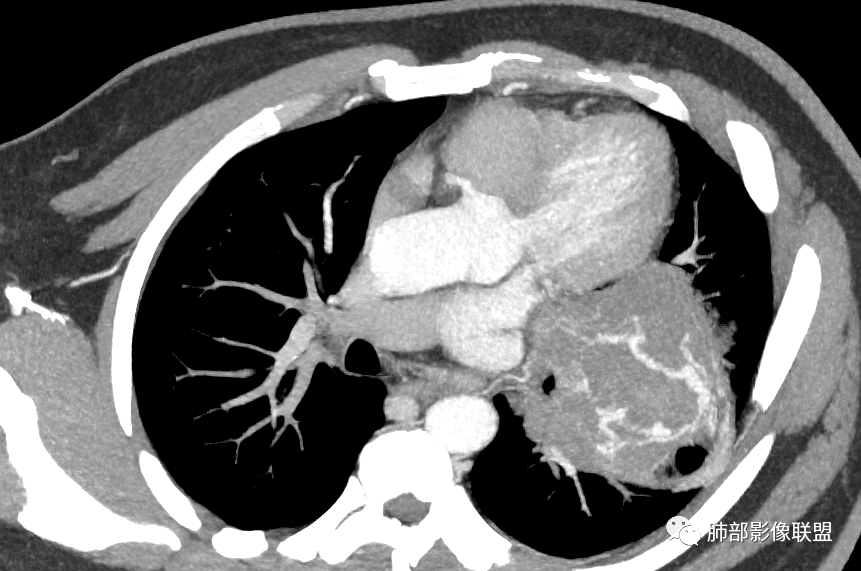

下肺静脉:

还是肺动脉供血,肺静脉引流

青年男性,体检发现左肺不规则类圆形占位性病变,叶间裂区域,定位胸膜来源。左肺下叶支气管受压狭窄,但管壁光整,未见腔内阻塞或管壁受侵。包块边界清晰,浅分叶,内部密度不均匀,病灶后份见空气新月征。渐进性强化,增强动脉期见分支状血管,蛇纹血管征。肺门纵膈未见增大淋巴结,符合孤立性纤维瘤(SFT)。

5)肿瘤的强化程度及方式:增强扫描肿瘤早期实性成分呈不均匀斑片或斑驳样强化,亦可呈“ 地图样” 明显强化,强化程度不一,可呈轻度-显著强化;静脉期持续强化,多期增强及动态增强扫描均呈“快进慢出”型强化,且强化范围逐渐增大并趋均匀。肿瘤内部及周围常见多发粗细不等强化或流空肿瘤血管影。瘤体内“蛇纹血管”在其他诸如硬化性肺细胞瘤、错构瘤等等是非常罕见的。